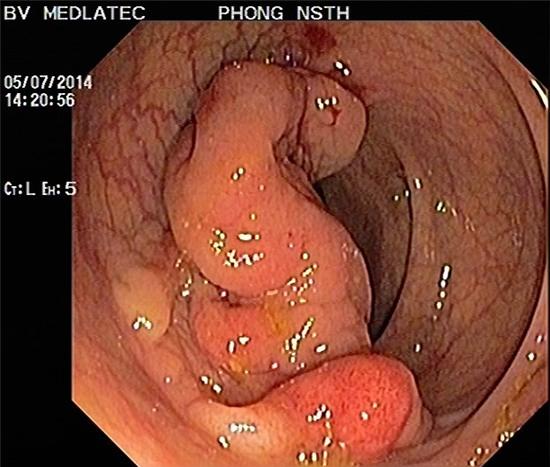

Một vài trạng thái bệnh lý được coi là tổn thương tiền ung thư, viêm loét đại trực tràng mãn tính có thể phát triển thành ung thư từ 20 – 25%, bệnh viêm mô hạt mãn tính của ống tiêu hoá, các u lành tính là những khối polyp kích thước lớn có nguy cơ K hóa rất cao.

Ngoài ra, có thể nội soi đại – trực tràng ống mềm, soi vào bên trong bằng ống mềm để nhìn rõ, có thể xác định các tổn thương trong đại tràng, sinh thiết, chẩn đoán bệnh sớm giúp người bệnh được điều trị kịp thời.